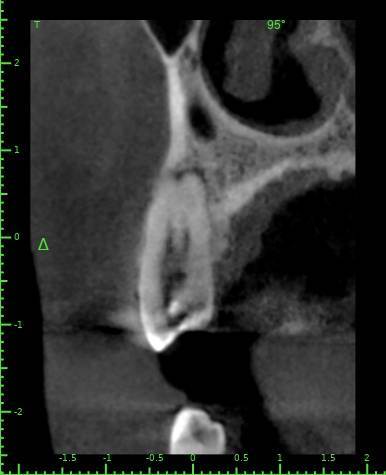

Здравствуйте, появился полгода назад свищ на десне, заполняется и лопается, затягивается и снова появляется, спустя пару месяцев обратился в стоматологию, на снимке ничего критичного не увидели, отправили домой наблюдать тип, еще прошло 3 месяца, так и не проходит и хуже не стало, болей нет никаких, только небольшая если трогать в районе свища, пойдя в другую стоматологию, сделали снимок и так же непонятно что и почему, пошел на КТ, и обратно в стоматологию, есть какая то полость, можно попробовать но нет гарантии, что пройдет, прикрепляю снимок К

ТРезультаты и плюс программа для открытия